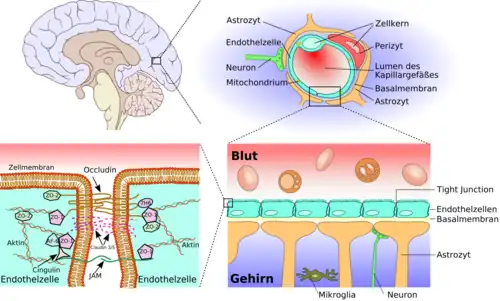

Konzepte zur Überwindung der Blut-Hirn-Schranke ermöglichen es, dem Gehirn für therapeutische Zwecke Wirkstoffe zuzuführen. Die Blut-Hirn-Schranke ist eine dynamische Grenzfläche, die über Influx (Zufluss, wörtlich: Einströmen) und Efflux (Abfluss) kontrolliert, welche Nährstoffe, Arzneistoffe, Drogen, Xenobiotika und sonstige Verbindungen dem Gehirn zugeführt werden können.[1] Dadurch gewährleistet sie dem Zentralnervensystem (ZNS) ein optimales Milieu.